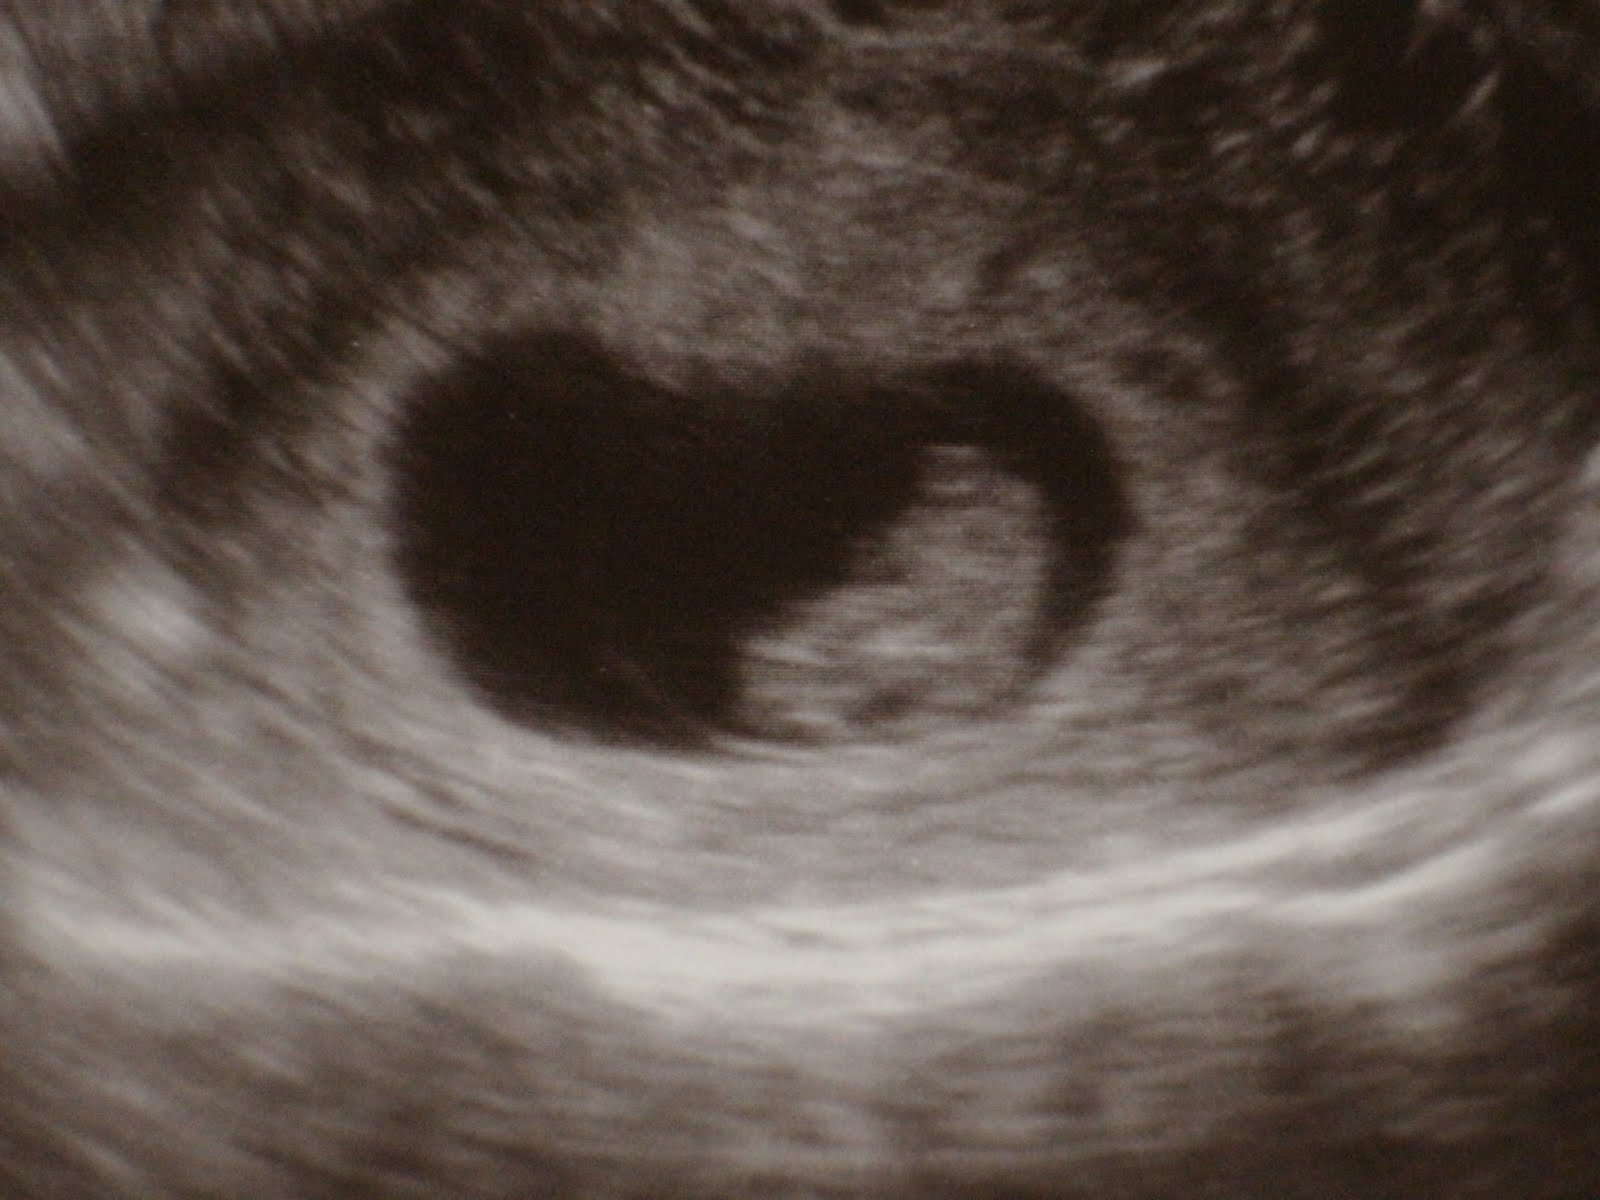

How far along: 8 weeks!

How big is Baby: The size of a raspberry! 1/2 an inch long.

Best moment this week: My first OB appointment, and seeing our baby for the first time! He had a great heartbeat: 177/min! It was such a thrill to see that little peanut in there doing so well.